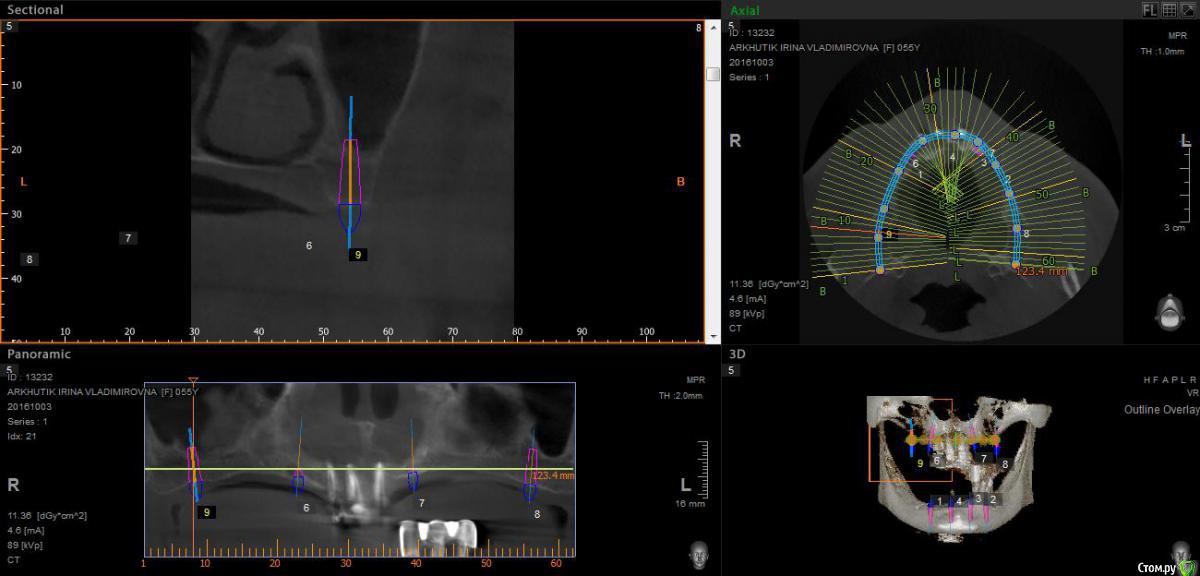

Rusty Опубликовано 5 октября, 2016 Поделиться Опубликовано 5 октября, 2016 Добрый день. К ортопеду обратилась пациентка 55-60 лет с такой ситуацией. Пришла с дочкой, дочь с мамой настаивали на несьемной конструкции, ортопед отправил на кт и вот. Не хочу планировать ей много хирургии, оцените и мой план пожалуйста и буду рад услышать советы по реабилитации пациента. По сути да) просто искал место куда есть возможность поставить, ортопед говорит тогда балка либо локаторы Ссылка на комментарий

Rusty Опубликовано 5 октября, 2016 Автор Поделиться Опубликовано 5 октября, 2016 На н/ч балка? Какие измерения в дист отделах? На в/ч мало четырёх. По три бы.На н/ч балка, в дистальных отделах над каналом около 3мм. На вч условий для установки больше 4 не нашел) Ссылка на комментарий

Nazim_NV86 Опубликовано 6 октября, 2016 Поделиться Опубликовано 6 октября, 2016 А на низ кроме блоков больше рабочих методов не вижу. Ссылка на комментарий